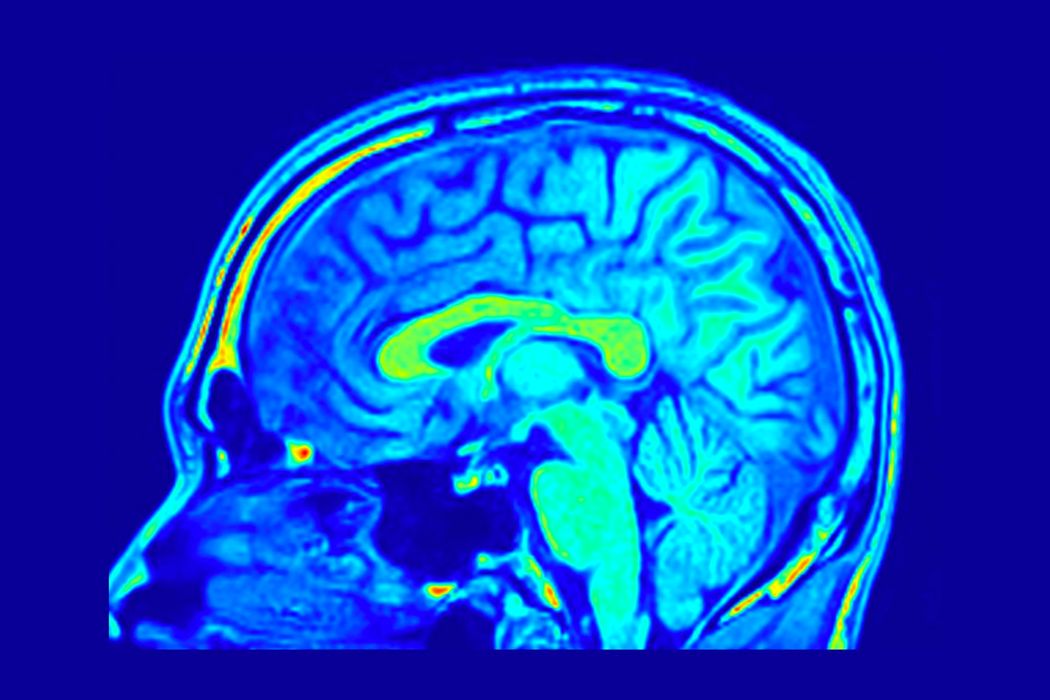

Un antidepresiv ar putea trata tumorile cerebrale

Glioblastomul este o tumoare cerebrală deosebit de agresivă, care în prezent este incurabilă. Medicii oncologi pot prelungi speranța de viață a pacienților prin operații, radioterapie, chimioterapie sau intervenții chirurgicale. Cu toate acestea, jumătate dintre pacienți […]